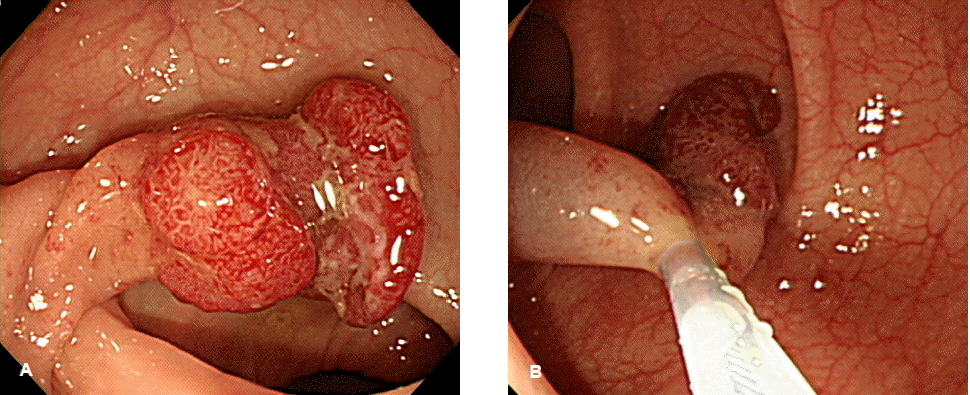

이런 기법들 중 조기대장암의 내시경절제술로 어떤 술식을 선택할 것인지는 조기대장암의 치료 원칙을 고려해서 판단해야 한다. 내시경절제술로 조기대장암의 완치를 기대하려면 충분한 절제변연(tumor-free resection margin)을 확보해야 하며, 절제된 조직이 정확한 병리학적 검토에 적합해야 한다. 이를 위해서는 일괄절제가 중요하다. 일괄절제 되어야 국소 재발을 예방하고, 절단면의 적절한 조직병리학적 평가가 가능하기 때문이다14-16). 이러한 조기대장암 내시경치료 원칙의 관점에서 볼 때 병변의 크기가 1~2 cm 이하로 작거나 뚜렷한 경(stalk)이 있는 경우에는 올가미절제술로도 일괄절제가 가능하므로 올가미절제술을 시행해 볼 수 있다(그림. 1)12). 그러나 병변의 크기가 2~3 cm 이상이면서 무경성인 경우에 올가미절제술을 시도하면, 일괄절제되지 못하고 분할절제되거나 절단면에 종양이 남는 경우가 49~79%나 된다12,16,17). 이와 같이 분할절제될 경우, 절제 표본 재구축의 어려움으로 정확한 조직병리 검사가 어려워 절단면 및 점막하층 암세포 침윤 판정 오류를 초래할 수 있다. 그러므로 조기대장암의 내시경절제술 기법으로 분할절제는 적절하지 않다18,19). 따라서 일본 대장암연구회에서도 조기대장암이 의심되면서 2cm 이상으로 큰 경우에는 완전절제의 가능성을 신중히 고려하여 내시경절제술 기법을 선택하도록 권고하고 있다20).

Figure 1.

(A) A polyp is seen in the sigmoid colon. Its ulcerated nonstructural mucosal surface suggests cancerous change. (B) The lesion can be resected easily by snaring because of the definite stalk.